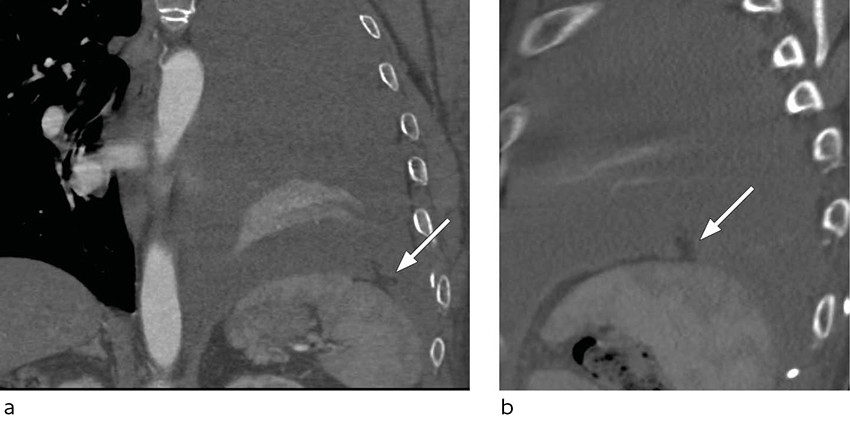

Etter to dagers behandling med alteplase ble pasienten utilpass med smerter i venstre hemithorax. Symptomene lettet da han la seg i sengen. Det ble like etterpå målt blodtrykk på 130/80 mm Hg, puls på 70 slag/min, perifer oksygenmetning på 97 % og registrert 400 mL blodig væske i drenposen. Noen timer senere ble pasienten igjen utilpass, og det ble målt blodtrykksfall til 55/30 mm Hg. Kontroll av hemoglobin viste et fall fra 9,4 til 8,2 g/dL i løpet av dagen. Tilstanden stabiliserte seg med intravenøs væskebehandling og en enhet erytrocytter. Pasienten var våken og blek, og blodtrykket var 100/60 mm Hg. Røntgen thorax viste tiltagende pleuraeffusjon (figur 1), og påfølgende CT thorax konstaterte massiv hemothorax med forskyvning av mediastinum samt en blødningssuspekt lesjon i relasjon til diafragma (figur 2). Tilbake på avdelingen hadde pasienten tiltagende takykardi med puls på 118 slag/min. Blodtrykket var 110/72 mm Hg. Det ble lagt et 28 french-pleuradren akutt og tappet én liter blod.

Ved videoassistert torakoskopi samme kveld fant man anterolateralt blødende oment gjennom en defekt i diafragma. Torakoskopisk fjernet man det blødende omentet og lukket defekten. Pasienten ble samtidig laparoskopert uten funn av ytterligere lesjoner i abdomen. Det postoperative forløpet var ukomplisert, og pasienten ble utskrevet i velbefinnende syv dager etter inngrepet.

I denne kasuistikken ga behandlingen vesentlig forverring av pasientens tilstand før den tilgrunnliggende årsaken ble identifisert og korrigert. Fibrinolysebehandling ble foretrukket på grunn av tiden siden traumet og pasientens klinisk stabile tilstand og betydelige komorbiditet, herunder diabetes og pankreatitt. Ved gjennomgang av CT-bildene fra den første innleggelsen og de senere røntgenbildene ses ikke tegn til diafragmaruptur. Diagnosen er sjelden og kan være klinisk og radiologisk vanskelig å stille, men bør overveies hos pasienter med relevant høyenergitraume (3).